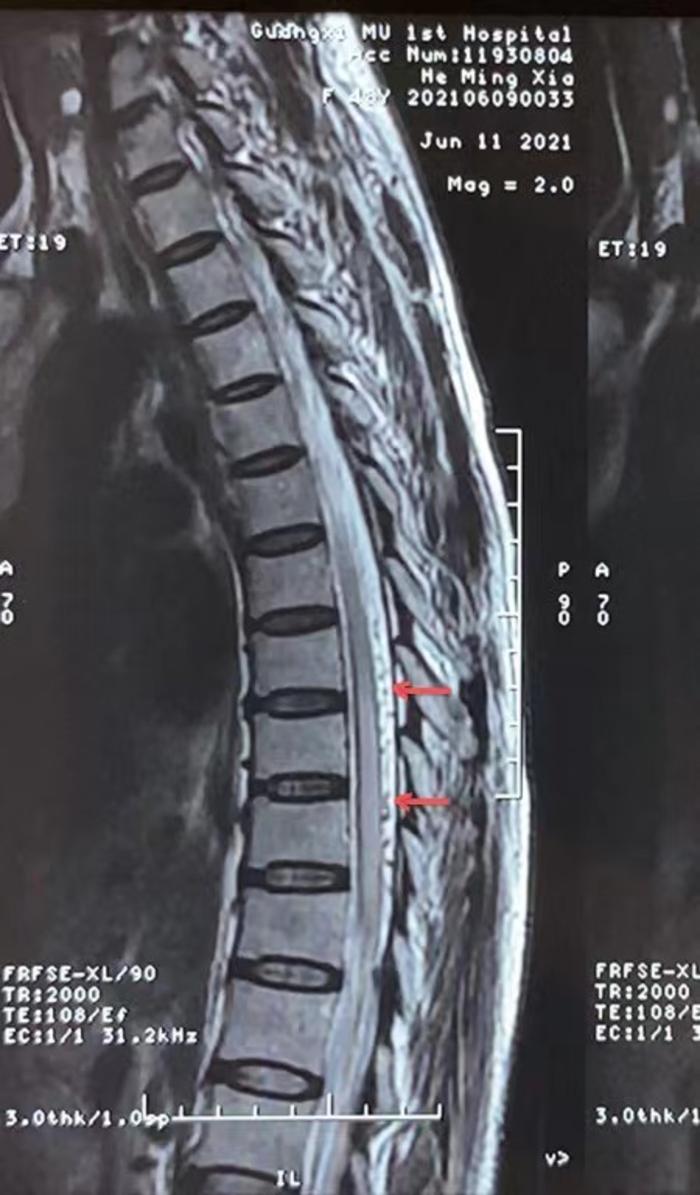

患者女,48岁,广西人,定居海南,自觉双下肢发力发软、麻木、无力,伴有小便困难,大便便秘一年余。在当地大型三甲医院检查胸腰椎MR提示脊髓背侧增粗迂曲血管影,脊髓水肿,高度提示脊髓血管畸形可能。在某医科大学第一附属医院行脊髓血管DSA造影阴性,没有发现异常。症状逐渐加重,来到我院门诊已经坐上轮椅了,患者痛苦不堪。

为积极挽救患者脊髓神经功能,戴大伟副主任医师团队第一时间收治患者入院,行全脊髓血管DSA造影明确左侧髂内动脉分支动脉供血的S1-2骶管硬脊膜动静脉瘘(SDAVF)